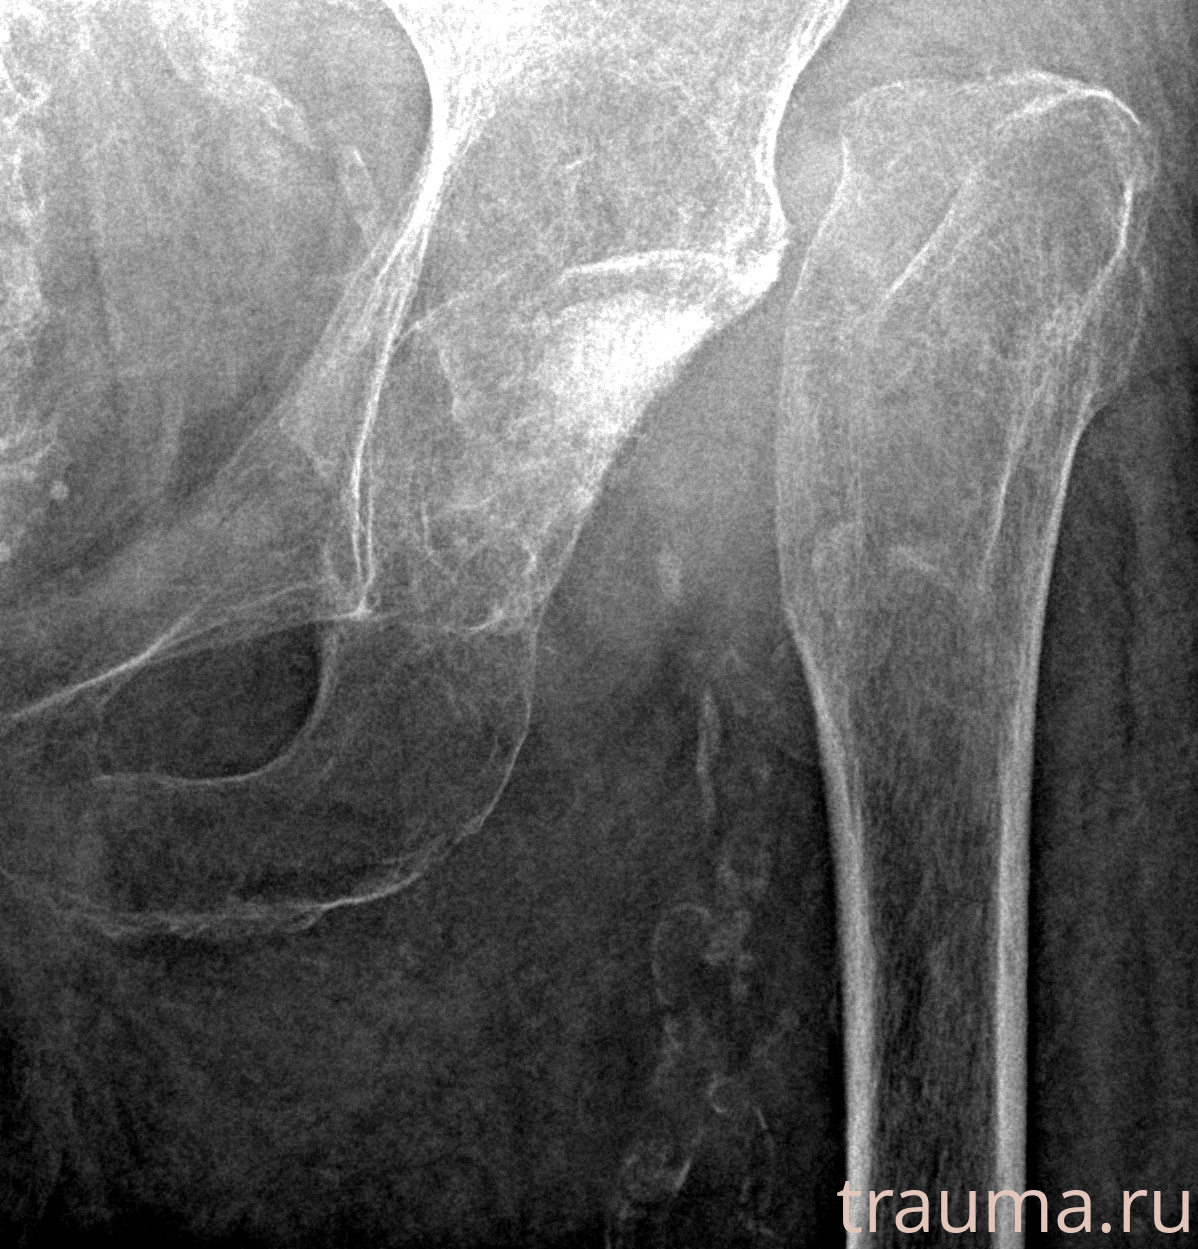

Рентгенограммы

Рентген на дому: по вашему адресу приезжает врач-рентгенолог, травматолог-ортопед с мобильным рентгеновским аппаратом, проводит диагностику травмы или заболевания, делает необходимые рентгенограммы, дает рекомендации по дальнейшему лечению. Получить качественные снимки в домашних условиях возможно благодаря уникальной методике, разработанной МосРентген Центром для института  Склифосовского